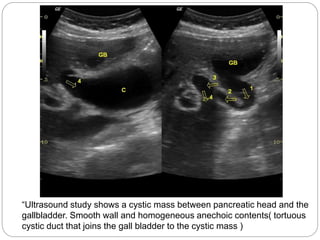

“Ultrasound study shows a cystic mass between pancreatic head and the

gallbladder. Smooth wall and homogeneous anechoic contents( tortuous

cystic duct that joins the gall bladder to the cystic mass )

“Ultrasound study showsa cystic mass between pancreatic head and the gallbladder. Smooth wall and homogeneous anechoic contents( tortuous cystic duct that joins the gall bladder to the cystic mass )